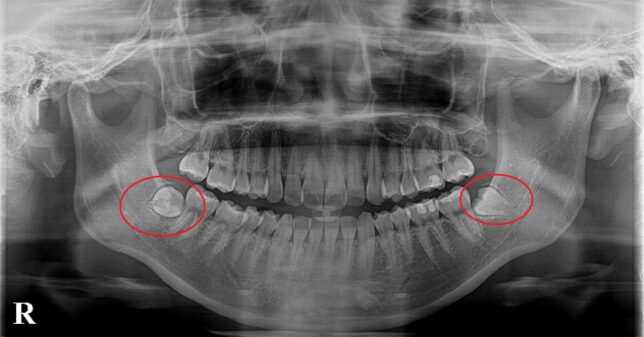

レントゲン写真を撮影しました。 親知らずは、横に向いて埋まっています。